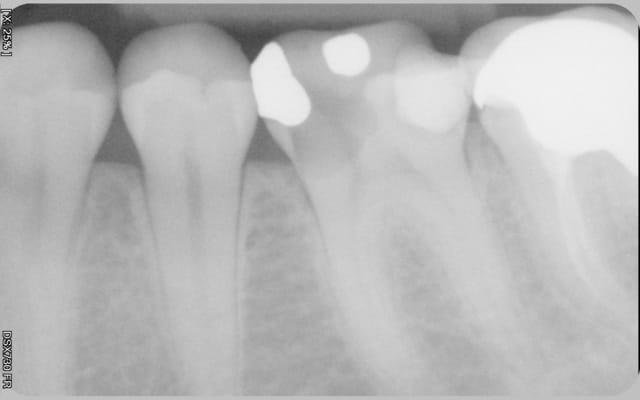

Re-belotte. 15.

et un bon vieux mordu, le tout 40 mn productivité !))))